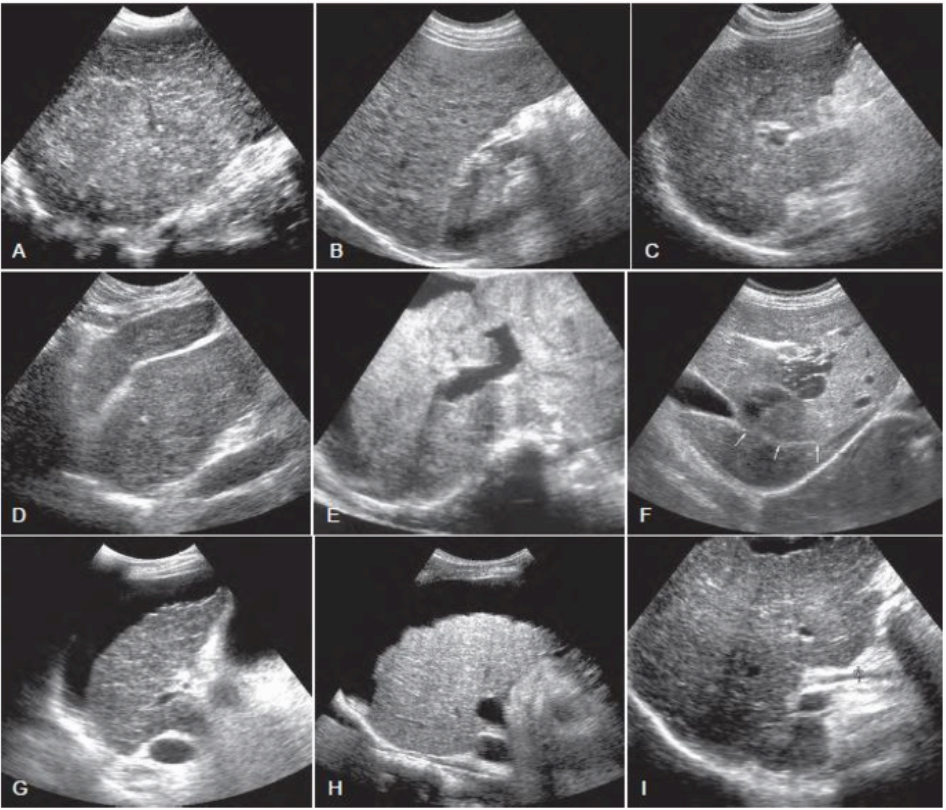

간경화증 (Liver cirrhosis) 간경화증(Liver cirrhosis)이란 지속적이고 반복적인 간손상으로 인해 간세포의 섬유화와 재생결절이 형성되는 질환으로 간기능 부전을 동반한다. 복수, 식도정맥류, 간성뇌증, 간세포암을 합병하며 간 전체에 걸쳐 재생결절과 글리슨씨초(Glisson sheath)를 중심으로 한 간질성 중격으로 간소엽의 변형을 보인다. 전형적인 초음파 소견으로는 간우엽의 위축, 좌엽비대 혹은 양엽 위축, 재생결절에 의한 간표면의 불규칙, 요철, 간연의 둔화, 간실질 에코가 거칠며 간정맥의 협소, 직경 크기가 불규칙하게 보인다.

또한 문맥압 항진에 동반하여 비장종대, 복수, 담낭벽 비후, 문맥 측부혈행로가 관찰된다. 간실질에코는 거칠고 조잡한데 이는 B형 간경변증에서 뚜렷하며 mesh pattern으로 불리는 그물코 모양의 에코가 관찰된다. C형 간경변증에서는 간실질에코가 비교적 균일하고, 알코올성 간경변증에서는 재생결절이 직경 3mm 정도로 균일하게 배열되어 있기 때문에 간실질 에코가 거칠지 않고 간표면의 요철도 초음파영상에서 거의 관찰되지 않는다. 또한 간종대도 양엽종대인 경우가 많으며 뚜렷하게 진행된 경우가 아니면 우엽의 위축도 관찰되지 않는다. 복수의 유무는 간경변증이 대상성인지 비대상성인지를 판정하는 데 있어 중요하며 소량의 복수 저류부위인 모리슨낭(Morison's pouch), 비장주위(좌횡격막하강), 소골반강을 관찰해야 한다. 특히, 활동이 자유로운 환자에서는 복수가 중력의 방향, 즉 소골반강에 저류해 있으므로 초음파 검사에서는 하복부의 스캔도 반드시 필요하다.

간경화증 (Liver cirrhosis) - 간 전체의 변형 (우엽 위축, 좌엽종대)

- 간표면의 불규칙한 요철

- 간실질 에코가 거칠고 불규칙하다

- 간정맥 불분명화 (직경 불규칙)

- 비장종대(splenomeglay)

- 문맥계 (간문맥, 비장정맥)의 확장

- 측부혈행로(제방정맥, 단위정맥, 좌위정맥, 비장 신장의 단락로)

- 담낭벽 이중상 또는 비후상 (문맥압 항진)

- 복수(ascites)

- 재생결절 (regenerative nodule)